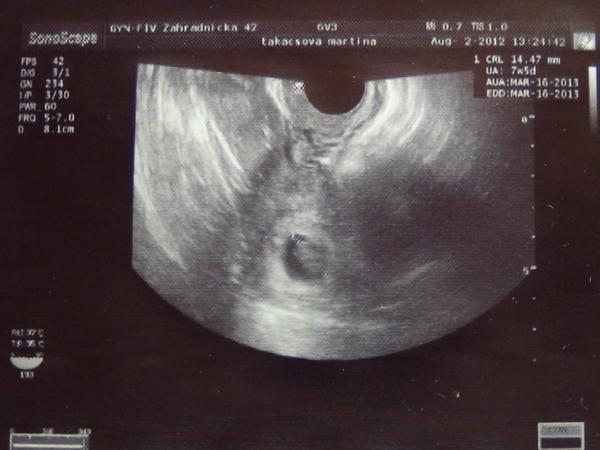

@dreamer1 ahoj, tiez som mala vlozene 3-dnove embryjko, teda morulu, ale veru ja mam pocit, ze sa zacalo uhniezdovat az okolo 10-14 dna,..lebo mne vysli testy na 11 a 13 den negativne a na 14 den bola krv pozitivna, aj ked hcg som mala nizke, takze musim ist na kontrolu, ci sa to vyvija dalej....ono aj ked sa zahniezdi, tak az ako blastocysta zacne do tela produkovat hcg. Asi treba byt len trpezlivy a vydrzat az do krvicky 🙂